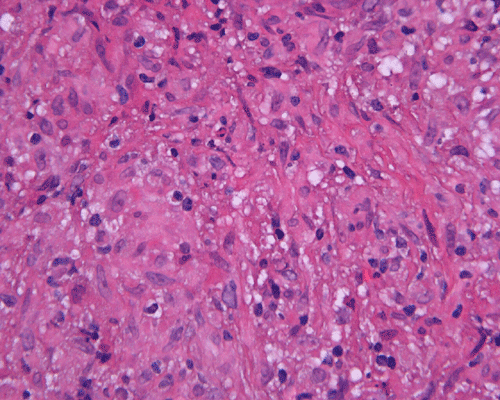

Paraffin sections: The entire volume of the tissue is made up of a granulomatous inflammation with poorly formed granuloma (Panel F, G, and H). The density of the lymphocytes is variable in different areas. In some areas, there is a rather intense lymphocytic infiltration accompanied by scant atypical cells with enlarged nulcei and prominent nucleoli (arrows in Panel I and J, Panel J is a higher magnification of Panel I). These atypical cells are quite easy to be missed. No microorganisms were identified by acid fast stain, PAS stain or GMS stain. The lymphocytes but not the atypical cells are positive for CD20 (Panel K) or CD3 (Panel L). The granulomatous background is strongly positive for CD68 (Panel M). Only rather faint positive staining for placental alkaline phosphatase (PLAP) is demonstrated and the interpretation is difficult as they are present in areas with crush artifact (Panel N). Many of the large, atypical cells are positive for CD117 (c-kit) (Panel O).

Immunohistochemically, the neoplastic cells show cytoplasmic membranous patten, sometimes diffuse cytoplasmic pattern, of staining for placental alkaline phosphatase (PLAP). Detection of c-kit (CD 117) in germinoma has been demonstrated and serves as a good diagnostic aid. Activating KIT mutations may contribute to tumorigenesis in germinoma 6, 7, 8. Syncytiotrophoblastic cells can be positive for human chorionic gonadotrophin (hCG). Occasional positive immunoreactivity for cytokeratin has been described and should not be taken as the sole evidence for embryonal carcinoma.